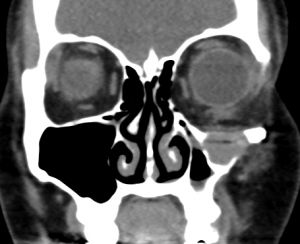

Postoperative imaging of orbital implants

Imaging of orbital fractures is indicated postoperatively to ensure accurate placement of orbital implants, occasionally when postoperative complications arise and when revision surgery is planned. This not only helps identify positioning of implants, but also assess orbital volume and soft tissue consequences and also guide additional surgery when indicated. While metallic implants are radioopaque and easily visible (figure 13 and 14) and easily visualized on bone and soft tissue windows, porous polyethylene implants and bioresorbable implants are more radiolucent and better visualized in soft tissue windows (Figure 15). Examples of suboptimal and good reconstruction with implant characteristics are shown below (Figure 16 and 17).